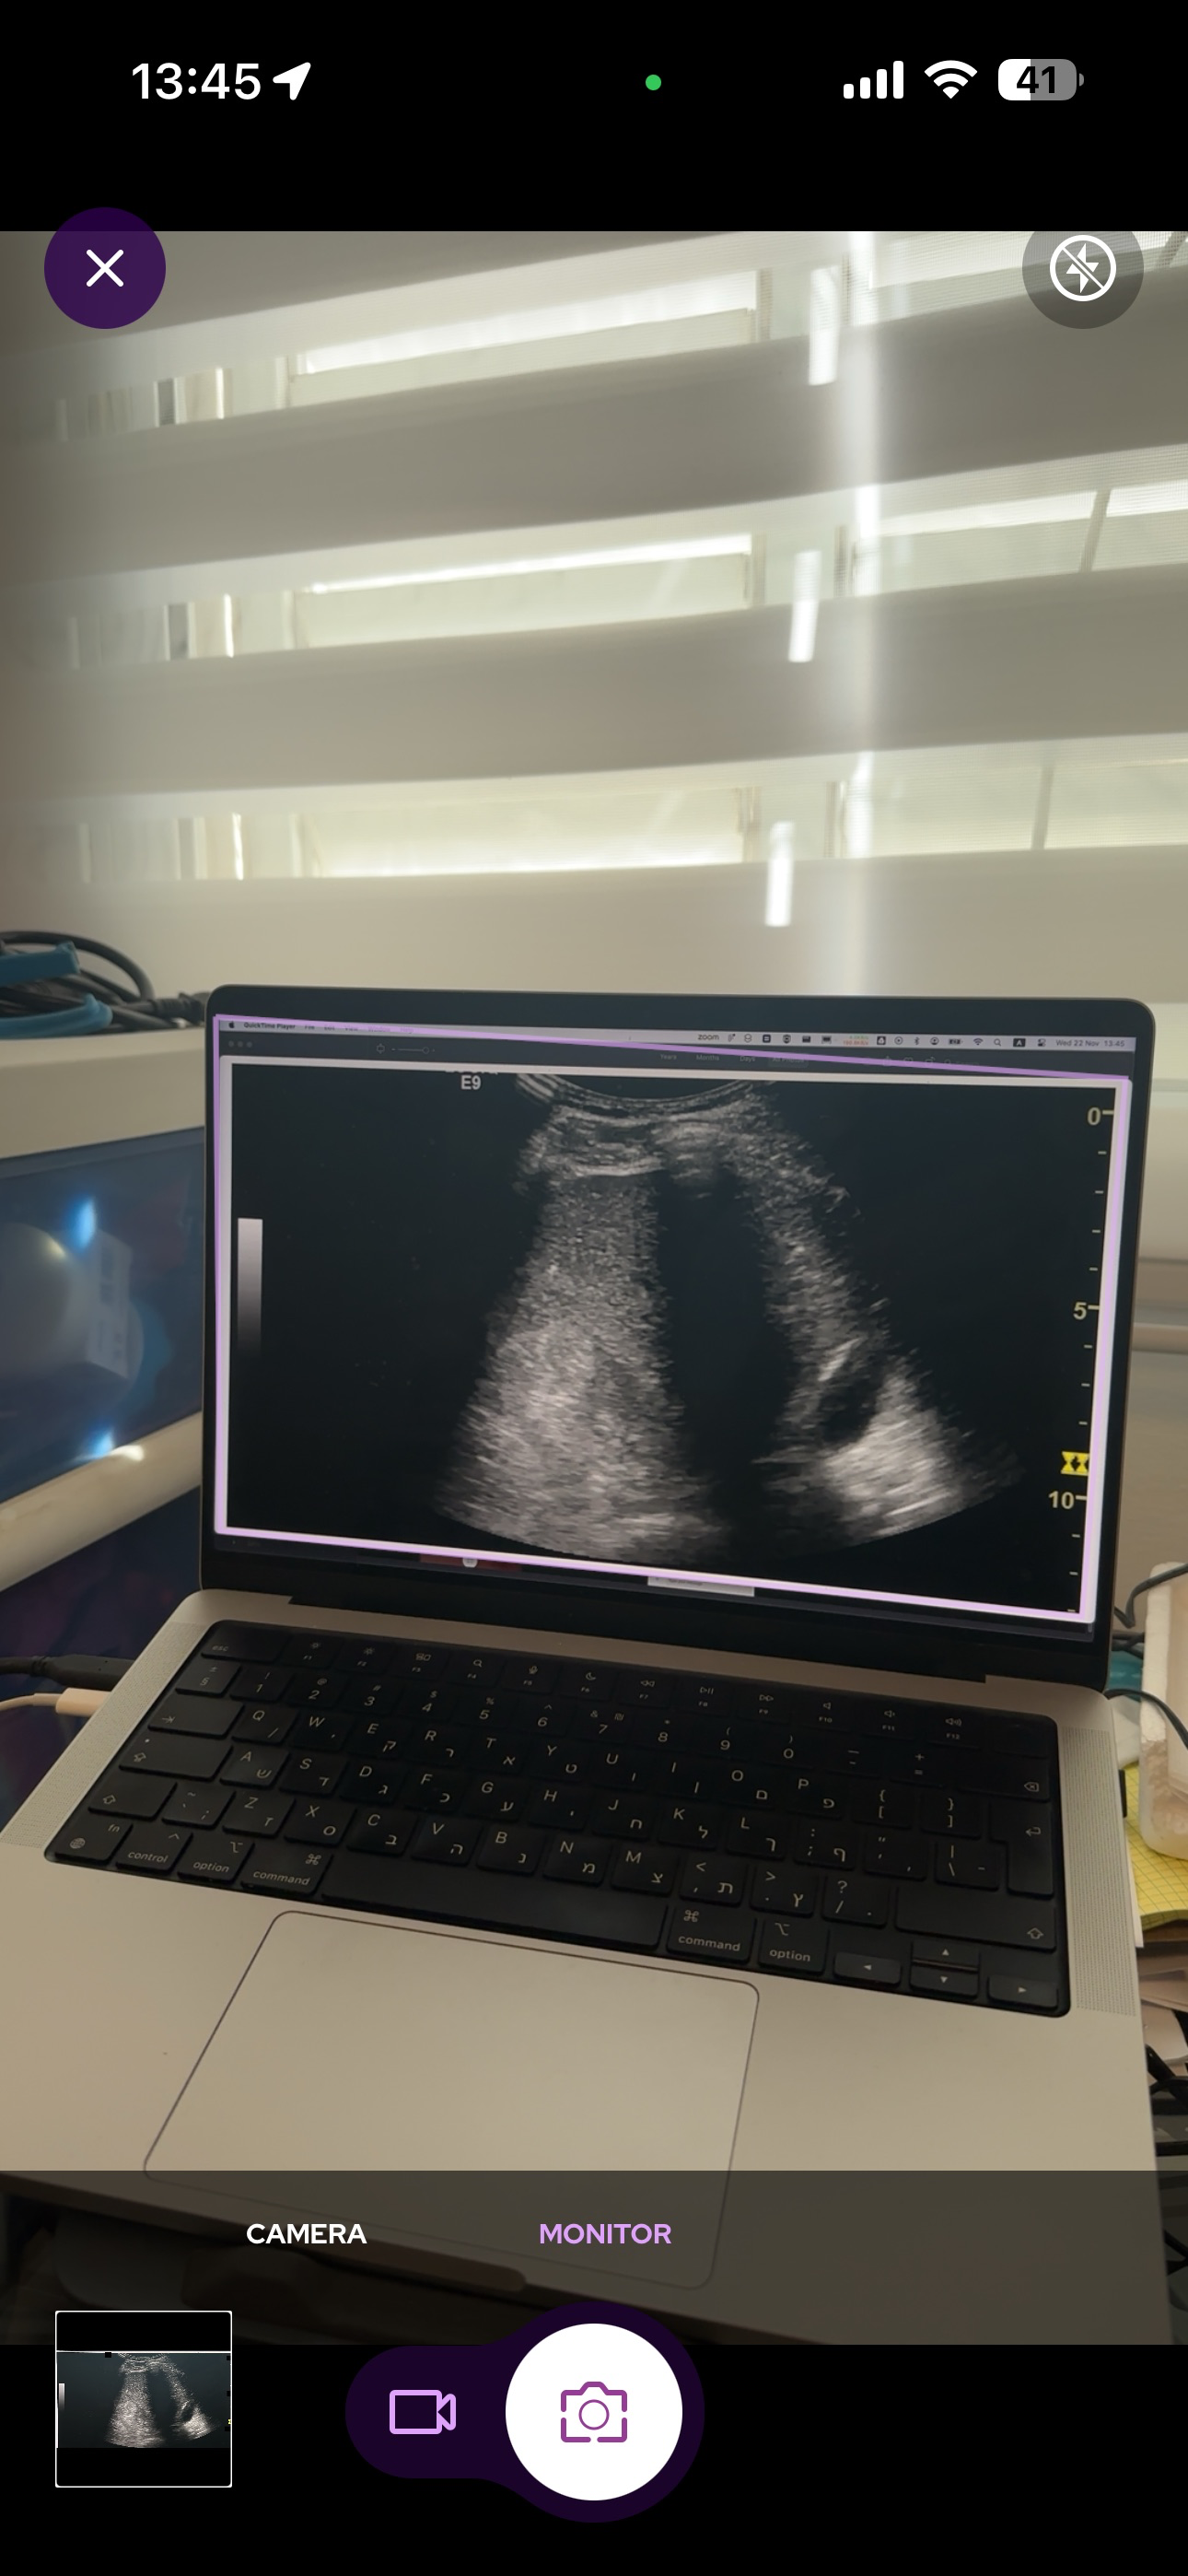

SeaGreen is a secure, open, free to use platform for healthcare professional to connect and collaborate. SeaGreen streamline consultation and collaboration such as AI powered capture mode that anonymize and a software virtual operating room.